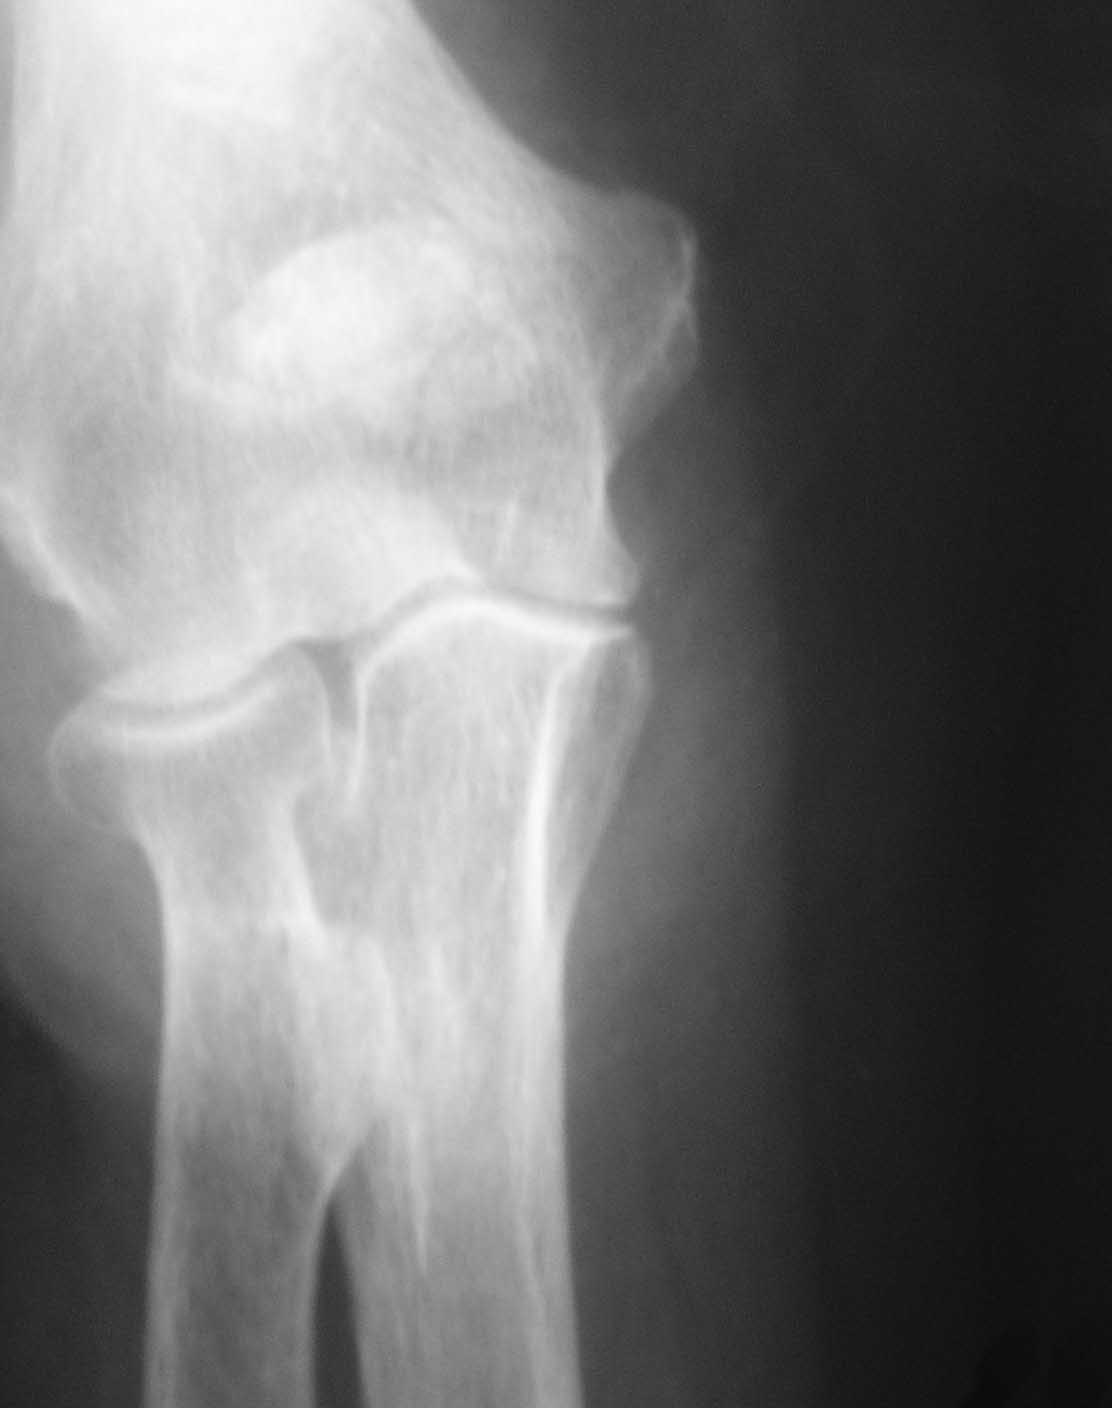

Обстоятельства дела. Пациентка Ш., 85 лет, поступила в отделение с оскольчатым переломом локтевого отростка с диастазом отломков. Из сопутствующей патологии: гипертоническая болезнь III ст.Б, АГ III ст, сахарный диабет, варикозное расширение вен н/конечностей, костный анкилоз левого локтевого сустава в порочном положении (после травмы более 30 лет назад). При более детальном осмотре рентгенограмм выявлен многооскольчатый перелом локтевого отростка с диастазом отломков, остеопороз (см. фото 1,2).

1) перелом - не оскольчатый, а раздробленный, с повреждением большей части локтевого отростка (С2 по А0, Тип IIIB по Mayo) с явлениями остеопороза, сминания промежуточных костных фрагментов. Подтверждением этому является наличие промежуточных костных фрагментов неопределенной формы, несоответствующей суставной части локтевого отростка, а также хорошо видимый передний подвывих костей предплечья (см. фото 2).